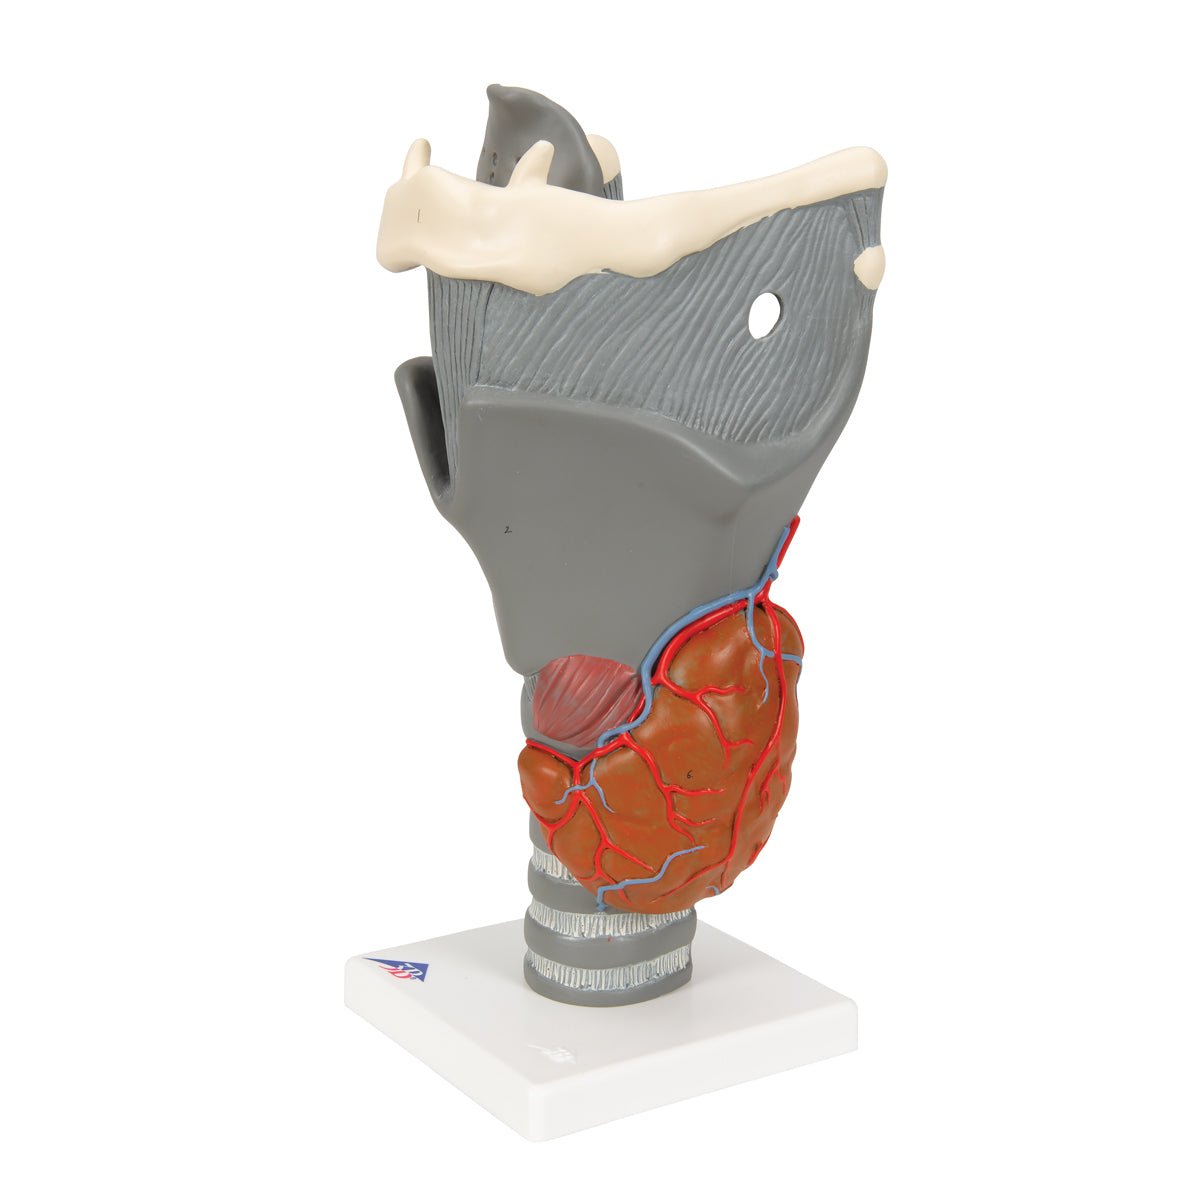

Anatomical models

Selling anatomical models is the mainstay of eAnatomi, although we also spend a lot of resources developing our own anatomical materials such as posters. Anatomical models are used for various purposes and can show both defined tissues, organs and organ systems. Are you looking for a simple model of bone tissue or perhaps an advanced torso model based on MRI technology, you can find it all at eanatomi.com.